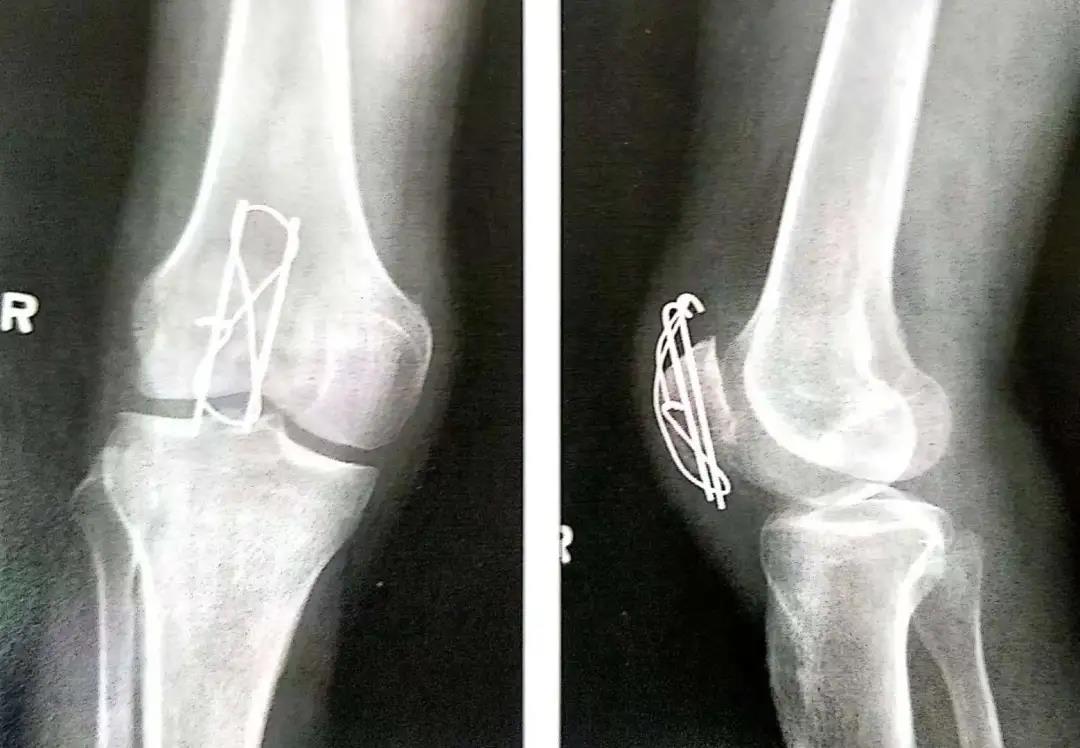

- 顺行或逆行打入克氏针。

- 克氏针或螺丝钉应在髌骨前皮质面下大约5mm打入,在骨质内冠状面和矢状面上相互平行。

- 在穿过骨折线之前,可用术中透视(正位和侧位)直视下或将手指伸到髌骨下触摸的方式来确保骨折已复位。

- 钢丝的两端在髌骨前面呈8字形交叉。张力带也可打成非交叉的方式。

- 两平行克氏针的末端剪断后在张力环上翻转180°,上下两端埋入骨内以防止其移位。